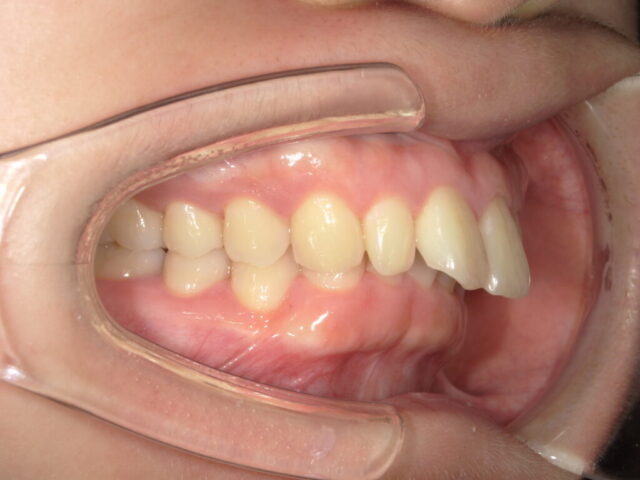

インビザラインによる開咬(オープンバイト)の改善

マウスピース矯正成人矯正

| 診断名 | 開咬(オープンバイト) |

| 治療期間・回数 | 1年7ヵ月 |

| 治療方法 | マウスピース型矯正(インビザライン)、非抜歯矯正 |

| 費用 | 935,000円(税込) |

| デメリット・注意点 | 使い始めやステージ変更時は締め付けられるような不快感が生じる場合がありますが、1週間前後で徐々に慣れていきます。 |